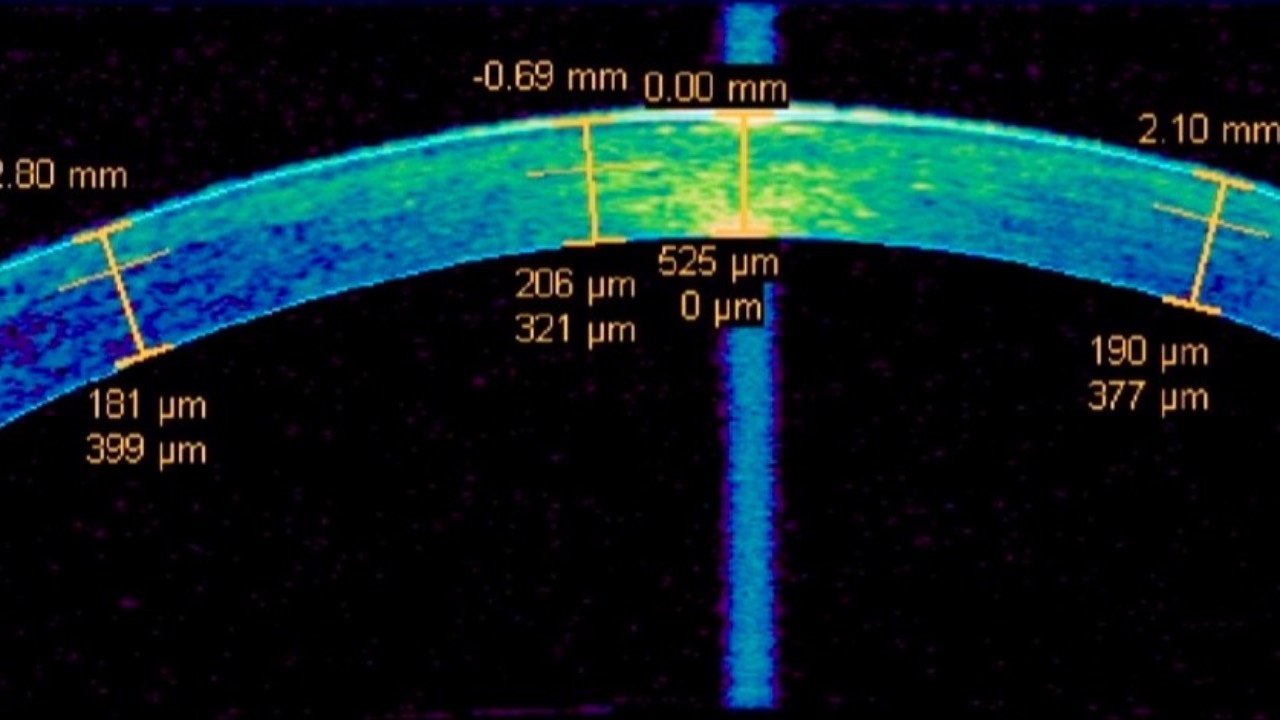

Thick Corneas & Increased Glaucoma Risk?

Maybe just throw away your pachymeter...

Contrary to our usual thinking, today the British Journal of Ophthalmology (BJO) released a powerful Mendelian randomization study revealing a positive correlation between central corneal thickness (CCT) and primary open-angle glaucoma (POAG). The research...